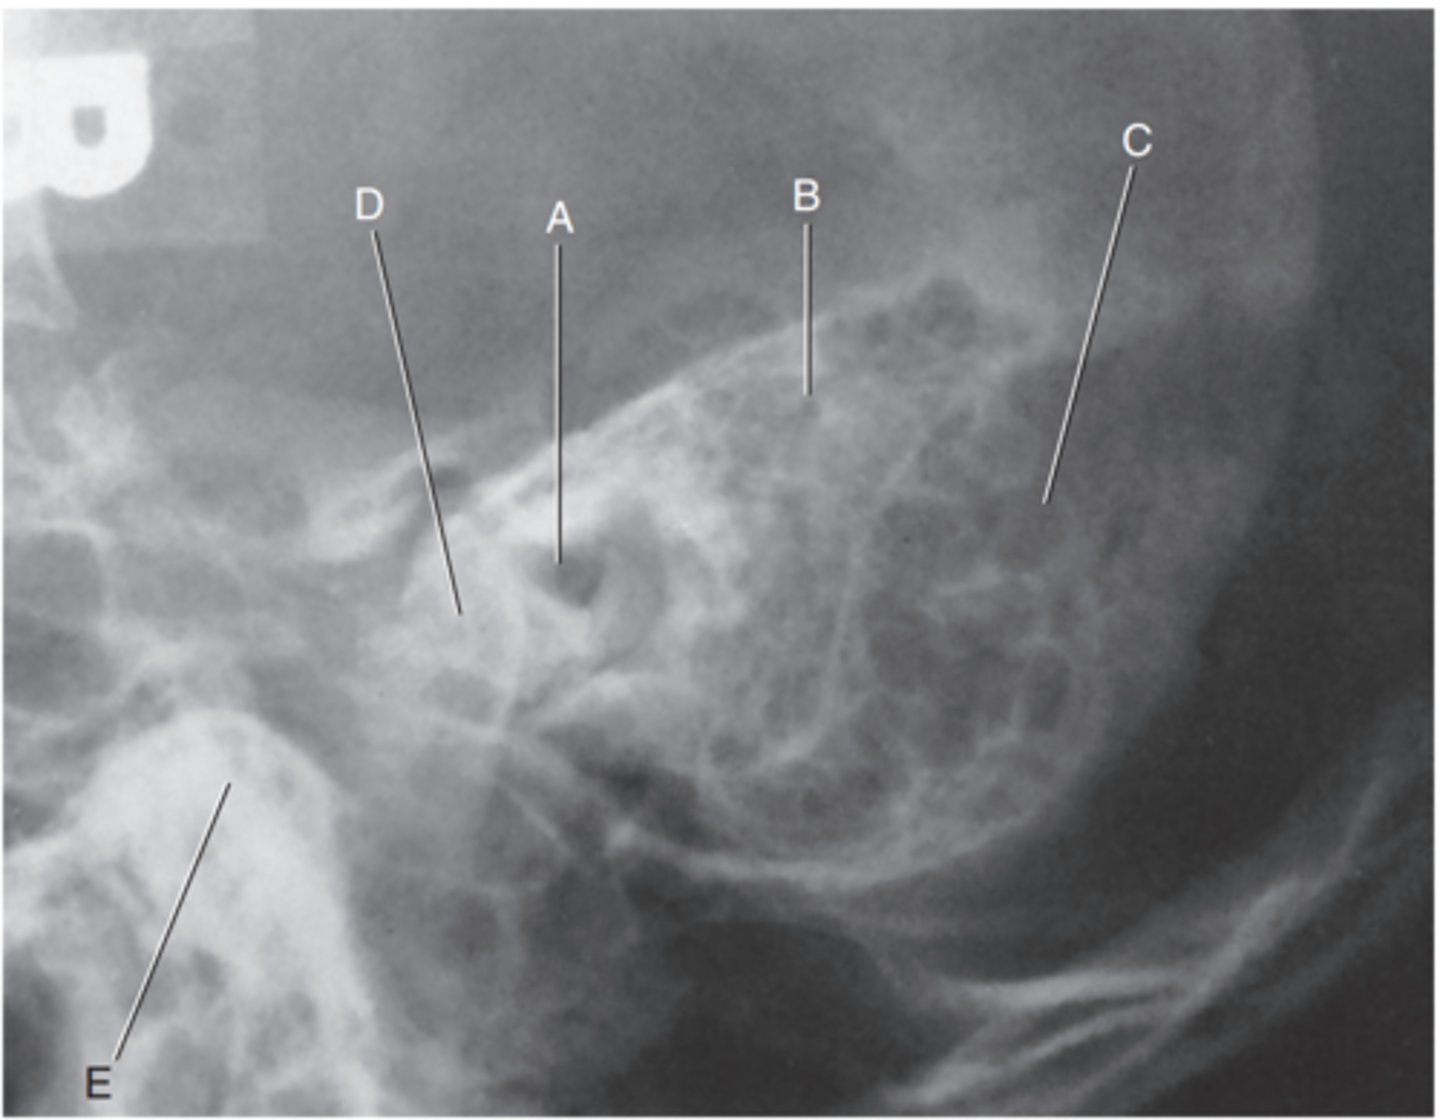

Petrous ridge

Label A

Bony (osseous) labyrinth (semicircular canals)

Label B

EAM

Label C

Region of internal acoustic canal

Label D